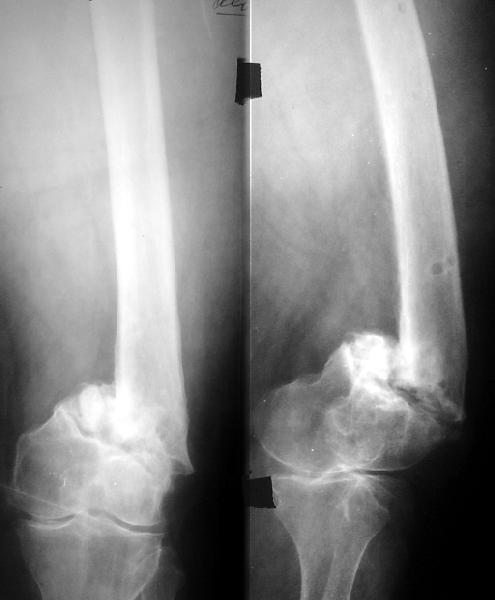

Пример подобного ложного сустава в приложении.

На сегодня есть имплантаты с куда более продвинутой дистальной фиксацией.